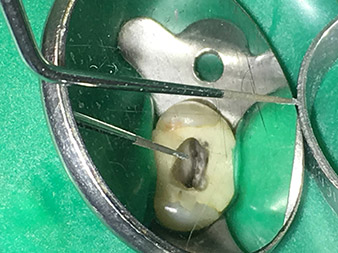

The 3E tip was specially designed for the removal of broken-off and fractured root canal instruments. In my experience, this is possible from the coronal section down to the central canal section with corresponding magnification (min. 3.6x dental loupes, ideally microscope).

This step should be performed with a non-diamond-coated, sharply tapered tip, with which it is possible to expose the fractured fragments of the instrument in the dentine region under microscopic control. In addition, the instrument is perfectly suited to exposing broken-off root canal posts coronally so that they can subsequently be shaken out with the 5E tip.

I also use this tip a lot to clear dentine overhangs away from thin canals and make the canal openings clearly visible. It is particularly well suited to applications in the second mesiobuccal canal on the maxillary molars or in cases of obturated canals. In the case of thin canals, the function is almost identical to that of the 6E tip, which works optimally in medium-sized to wide canals.

The 4E tip – this instrument is optimally suited to preparation of the cavity floor at the transition to the canals. It can be used to round off the transition between the canal and the cavity floor optimally so as to produce a funnel leading into the canal. In addition, the instrument is the ideal choice for removing dentine overhangs from canals.

All in all, the cavity can be prepared very efficiently and minimally invasively with this tip by optimally rounding off and smoothing overhangs, corners and edges.

Pictures: Dr. Shahrad Nouraie Ashtiani, Bremen